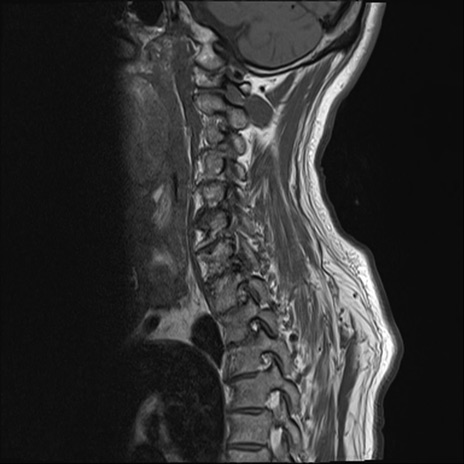

【整形】TIPS症例7 頚椎MRI T1WI(矢状断像)

頚椎MRI

T2WI(矢状断像)